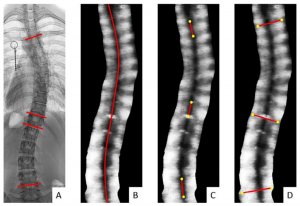

In ultrasound imaging of the spine, both the spinous processes (SPs) and transverse processes (TPs) were used to measure the coronal deformity. Both landmarks provided reliable information on the severity of the curve as related to the traditional Cobb angle. However, it remained unclear which coronal ultrasound angle is the most appropriate method to measure the curve severity. This study investigated the reliability and the validity of three Scolioscan angle measurement methods (1. Automatic SP angle; 2. Manual SP angle; 3. Manual TP angle) in the coronal plane as compared with the radiographic coronal Cobb angle in patients with AIS.

Radiographic coronal Cobb angle (A); Automatic SP angle (B); Manual SP angle (C); Manual TP angle (D)

Key Findings

- Excellent intra- and inter- reliability of all three measurement methods (ICC=0.84-1.00)

- All three coronal ultrasound angles showed excellent linear correlations with the Cobb angles (R2=0.970-0.992)